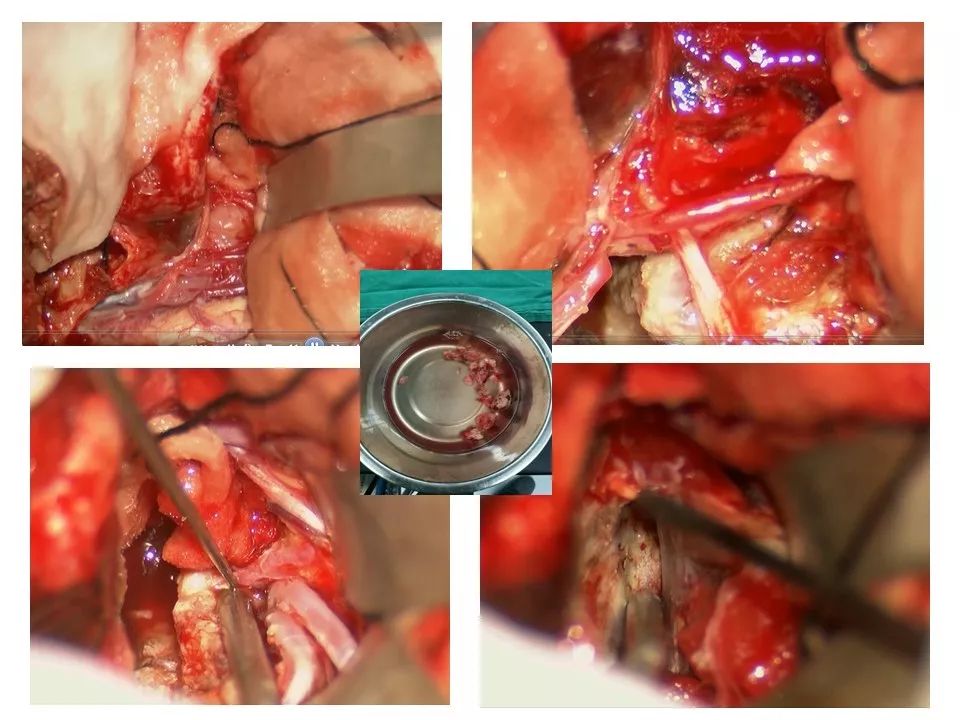

今天为大家分享的是《贝朗时间》第三十八期,由中国人民解放军武汉总医院神经外科副主任姚国杰教授带来的:远外侧入路全斜坡巨大脑膜瘤显微手术1例,欢迎阅读、分享!

远外侧入路全斜坡巨大脑膜瘤显微手术1例